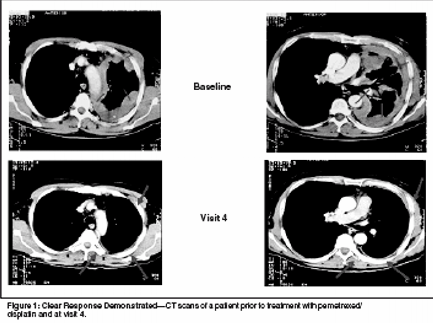

Figure 1 illustrates a CT scan of astudy patient prior to treatment withpemetrexed/cisplatin and at visit 4.These graphically illustrate a clear responseassociated with pemetrexed/cisplatin. Overall, the tumor responserate was significantly higher on thepemetrexed/cisplatin arm (41.3%)than in the patients who received cisplatin(16.7%). Differences in responserates were also significantbetween fully supplemented patientswho received pemetrexed/cisplatincompared with those who receivedcisplatin (45.5% vs 19.6%, respectively).Table 3 contains efficacy data forall patients and for fully supplementedpatients. Survival between the pemetrexed/cisplatin and cisplatin armswas also statistically significant, 12.1vs 9.3 months, respectively. Time todisease progression was 5.7 monthsin patients who received pemetrexed/cisplatin vs 3.9 months in patients whoreceived cisplatin monotherapy. Thisdifference was also statistically significant.[22]An analysis of this phase III studywas conducted by Symanowsi etal,[23] on prognostic variables affectingsurvival. Vitamin supplementation,good Karnofsky performanceptatus, early-stage disease, and epithelialsubtype were associated withimproved survival. This analysis demonstratedthat Karnofsky status, diseasestage, and histology werepowerful predictors of survival in patientswith MPM.[23]Another analysis of this trial includedevaluation of lung function andits correlation to tumor response.[24]Patients who experienced a tumor responsehad consistently better pulmonaryfunction tests than did patientswith stable disease; patients with stabledisease had better pulmonary functiontests than those with progressivedisease. Figure 2 shows changes inforced vital capacity of patients onthe pemetrexed/cisplatin and cisplatinsingle-agent arms of the study oversix cycles of therapy.Quality-of-life data in this studydemonstrated an advantage for thecombination of pemetrexed/cisplatinover single-agent cisplatin.[25] Usingthe LCSS-Meso instrument, globalquality of life, pain, dyspnea,fatigue, anorexia, and cough werecompared between the two arms. Themajority of these parameters reachedstatistical significance between thetwo arms by week 15, in favor of thepemetrexed/cisplatin arm (Figure 3).Manegold and colleagues identifiedthe incidence of post study chemotherapyamong patients in this trialand determined that 38% of patientswho received pemetrexed/cisplatinreceived post study chemotherapycompared with 48% of patients whoreceived cisplatin monotherapy. Themost commonly identified second-linetherapy was gemcitabine followed byvinorelbine and doxorubicin.[26] Aphase III trial of pemetrexed plus bestsupportive care (BSC) vs BSC as second-line therapy in patients with MPMis ongoing.DiscussionMany agents have been investigatedin the treatment of MPM with noclear standard of care emerging. Theantifolate class of agents shows themost promise of the agents investigatedin the treatment of this aggressivedisease. Recent data havedemonstrated that pemetrexed, as asingle agent and in combination withcisplatin, is an active agent with manageabletoxicity when folic acid andvitamin B12 supplementation is administeredconcurrently.Pemetrexed has demonstrated efficacywith toxicity that is manageablewith the addition of vitaminsupplementation. The combination ofpemetrexed/cisplatin significantlyimproved the survival in comparisonto cisplatin alone. Other analyses demonstratedsignificantly improved lungfunction and quality of life in patientswho received pemetrexed/cisplatincompared with patients who receivedcisplatin monotherapy. Supplementationwith vitamins demonstrated animprovement in toxicity and efficacy.